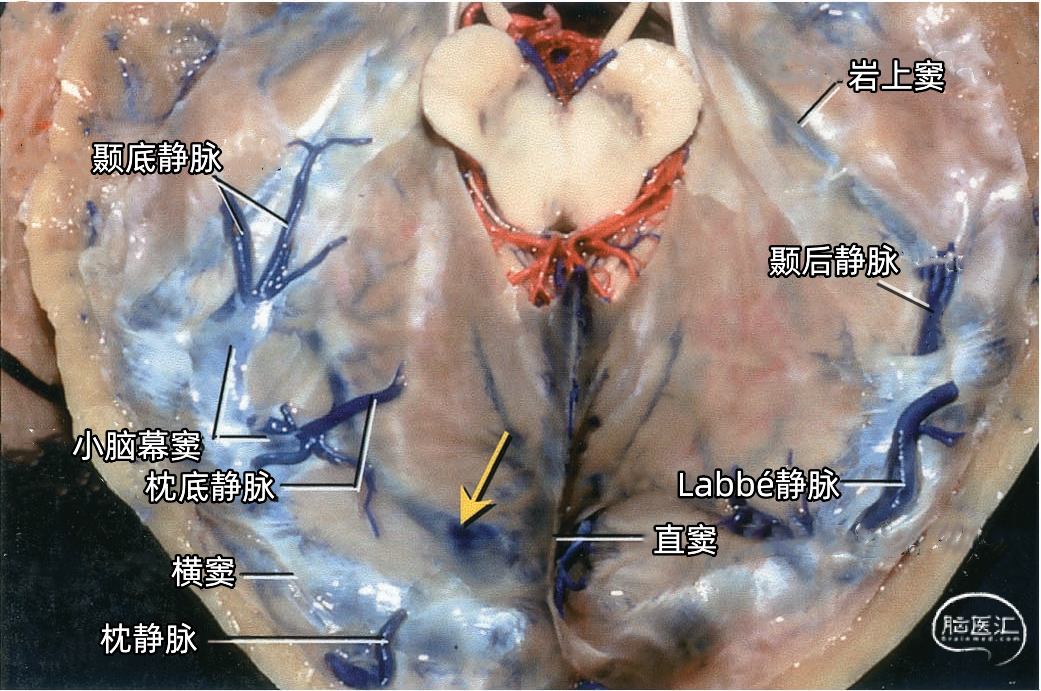

每侧小脑幕有两个恒定但不对称的静脉窦,即内侧小脑幕窦和外侧小脑幕窦。 内侧小脑幕窦由小脑上表面的回流静脉汇聚而成。内侧小脑幕窦向内侧引流入直窦,或直窦与横窦的汇合处。 外侧小脑幕窦由颞叶和枕叶基底面和外侧面的回流静脉汇聚而成。外侧小脑幕窦起自小脑幕的外侧部分,并向外侧引流入横窦的末端。 下图示抬起小脑幕,可见来自小脑、在小脑幕下缘入窦的桥静脉。左侧黄色箭头显示一支较大的静脉自小脑上表面进入内侧小脑幕窦。右侧红色箭头显示一支粗大的来自小脑上表面的桥静脉在窦汇前方进入内侧小脑幕窦。

下图示汇入外侧小脑幕窦的颞底静脉、枕底静脉。左侧红色箭头指示左侧汇入小脑幕窦属支的颞底长静脉。颞底静脉汇入有多个属支的小脑幕窦。右侧黄色箭头显示汇入右侧小脑幕窦的静脉属支。 下图示(左侧)颞底静脉和枕底静脉汇聚于两个横窦内侧的短小脑幕窦。(右侧)Labbé静脉和颞后静脉直接引流入横窦。左侧小脑幕的另一个窦(小脑幕内侧窦)(黄色箭头)接受来自小脑的引流,向内侧经过小脑幕汇入窦汇。

下图示右侧枕底静脉,颞底静脉。从后颞下入路抬起颞底到达小脑幕游离缘时,除了可能牺牲Labbé静脉和来自颞叶、枕叶外侧面的静脉外,还可能需要牺牲多条汇入小脑幕窦的颞底静脉和枕底静脉。

Labbé静脉也称下吻合静脉,是跨越颞叶外侧,连接外侧裂与横窦之间的最大吻合静脉。它通常起自外侧裂中部,行向后下,进入横窦前部。 Labbé静脉经过颞叶表面的位置有可能非常靠后甚至位于颞叶的最后界,或非常靠前达颞叶前1/3的外侧面。在此研究的20例半球中,12例Labbé静脉位于颞中静脉水平,6例位于颞后静脉水平,2例位于颞前静脉水平。有时会有两条Labbé静脉,其中后支通常会粗大一些。

下图示小脑幕的上面观。右侧Labbé静脉和颞后静脉直接引流入横窦。

小脑幕组(上图 绿色)的桥静脉汇入行经小脑幕的静脉窦,即小脑幕窦或小脑幕附近的横窦和岩上窦。本组静脉引流颞叶外侧面和底面、枕叶的底面,包括颞底静脉、枕底静脉和来自颞叶外侧面的降静脉,如Labbé静脉。 除Labbé静脉外,这些静脉虽然有可能进入横窦,但大多数围绕半球的下缘汇聚于枕前切迹到达外侧小脑幕窦。而Labbé静脉通常汇入横窦。大脑底面的桥静脉汇入静脉窦之前,经常粘连于与中颅窝底硬膜和小脑幕表面。 从外侧面引流入小脑幕窦的静脉包括颞前静脉、颞中静脉、颞后静脉和Labbé静脉。

从下表面引流入小脑幕窦的静脉包括颞底前静脉,颞底中静脉、颞底后静脉和枕底静脉。 内侧小脑幕窦接受来自小脑的静脉血流,并加入直窦。基底窦位于斜坡。 大脑镰组(上图 紫色)由直接或经由大脑内静脉、基底静脉和大脑大静脉汇入下矢状窦或直窦的静脉构成。汇入直窦的静脉(上图 紫色)或其属支,引流胼胝体附近部分的额叶、顶叶和颞叶内侧部,此组静脉的引流区域大致相当于大脑边缘叶,包括终板旁静脉,额眶后静脉、嗅静脉、胼周前静脉、胼周后静脉,钩回静脉、海马前静脉、颞内侧静脉和距状前静脉。